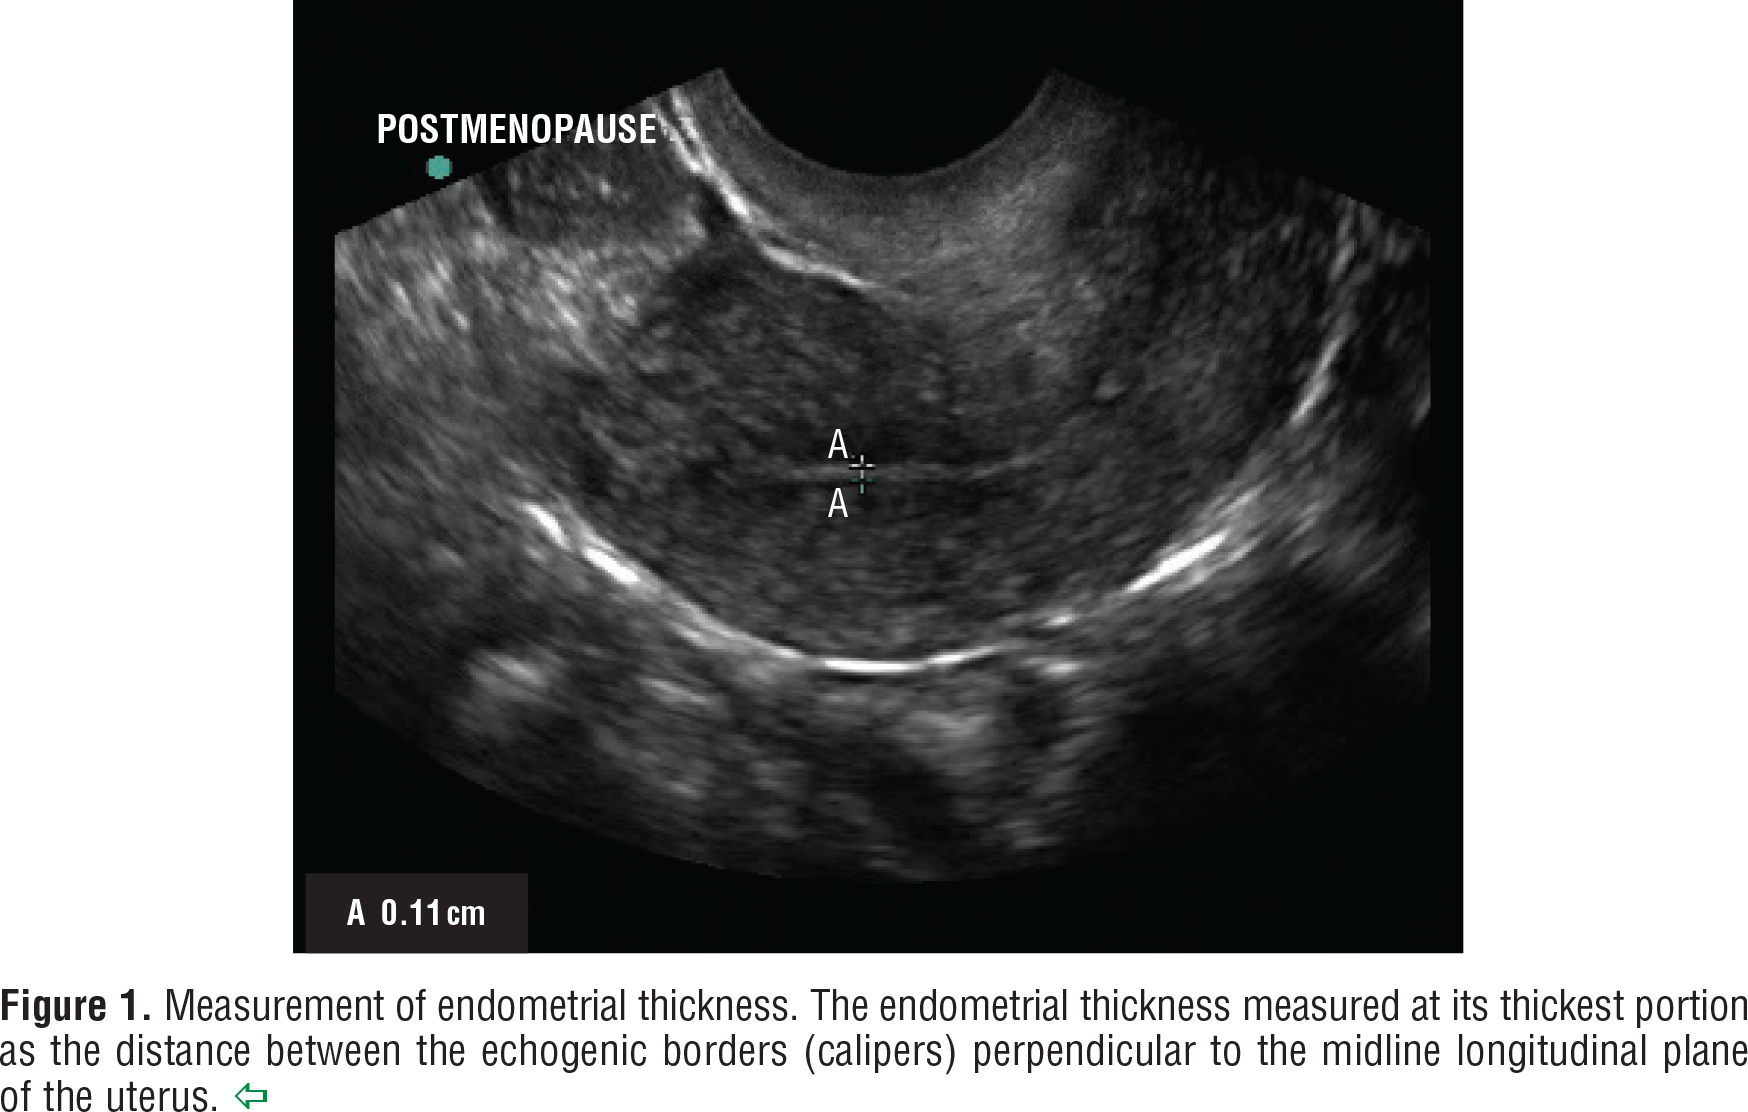

Endometrial thickness is measured as the maximum anterior–posterior thickness of the endometrial echo on a long-axis transvaginal view of the uterus. The earliest reports comparing transvaginal ultrasonography with endometrial sampling consistently found that an endometrial thickness of 4–5 mm or less in women with postmenopausal bleeding reliably excluded endometrial cancer 7 8 9. Since that time, a number of confirmatory multicenter trials have been completed Table 1. Transvaginal ultrasonography is appropriate for an initial evaluation of postmenopausal bleeding if the ultrasound images reveal a thin endometrial echo (less than or equal to 4 mm), given that an endometrial thickness of 4 mm or less has a greater than 99% negative predictive value for endometrial cancer.

It is not possible to complete a meaningful transvaginal ultrasound examination with a reliable measurement of endometrial thickness in all women 13 14. The thickest part of the endometrium should be measured perpendicular to its longitudinal plane in the anteroposterior diameter, representing the distance between the echogenic borders Figure 1 15. An axial uterus, obesity, coexisting myomas, adenomyosis, or previous uterine surgery can contribute to difficulty in obtaining reliable transvaginal ultrasound assessment of endometrial thickness and texture. Failure to adequately identify a thin, distinct endometrial echo in a postmenopausal woman with bleeding should trigger sonohysterography, office hysteroscopy, or endometrial sampling 10. In addition, endometrial fluid, when present, should not be included in measuring endometrial thickness. If an abnormal endometrium is identified, endometrial sampling is warranted.